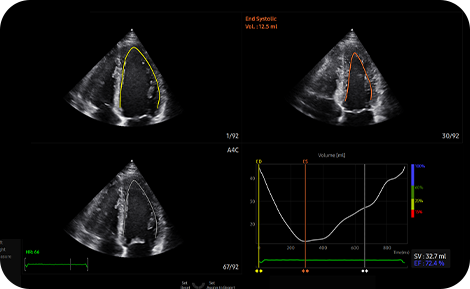

Measure Ejection Fraction of the

left ventricle conveniently

AutoEF is a feature which measures and quantifies Ejection Fraction. By selecting the three points of the left ventricle, the volume at the end-systolic and end-diastolic points of the left ventricle is calculated, to assist in quick and efficient assessment.

medical diagnostics : AutoEF